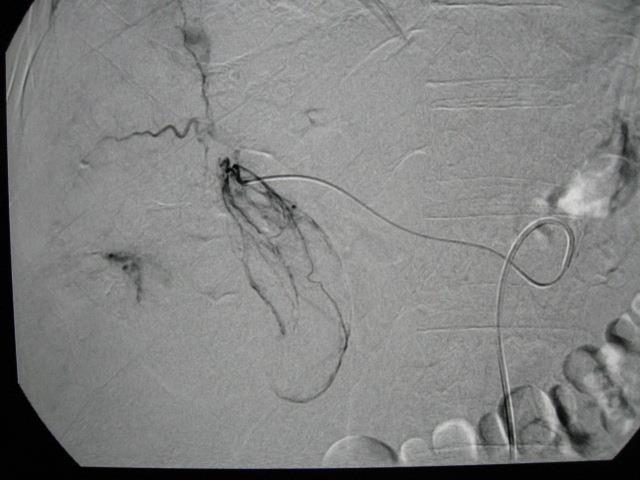

典型胆囊动脉

除了典型的胆囊动脉,胆囊动脉还存在一些罕见的变异。